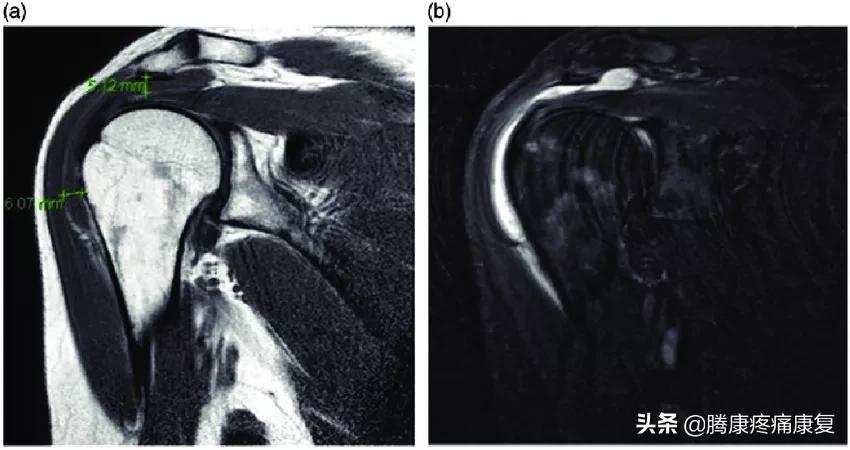

(a)接种疫苗7周后,对左肩进行T1磁共振成像(MRI)扫描,表明肩峰下和三角肌下滑囊炎,已用测量工具标记。(b) 接种疫苗7周后,对左肩进行T2 MRI扫描。在这里,充满液体的囊呈白色。